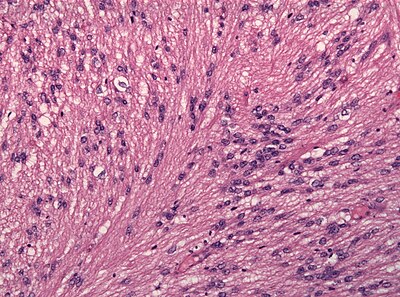

2

Diagnosis?

Myxopapillary ependymoma-HE.jpg

Pilocytic astrocytoma

Diffuse Astrocytoma

Pleomorphic xanthoastrocytoma

Subependymal giant cell astrocytoma

Oligodendroglioma

Glioblastoma, classic

Glioblastoma, epitheloid

Giant cell glioblastoma

Gliosarcoma

Ependymoma

Subependymoma

Myxopapillary ependymoma

Ganglioglioma

Choroid plexus papilloma

Angiocentric glioma

Dysembryoplastic neuroepithelial tumour

Neurocytoma

Paraganglioma

Pineocytoma

Papillary glioneuronal tumour

Medulloblastoma

CNS PNET